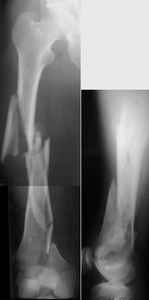

I presented a series of ~25 such cases at EuroTrauma'2004. Many cases were discussed here. I attach am example. Look also recent cases at http://www.hwbf.org/hwb/conf/alex58/scfx.htm,

THX, initial images are

1,

2.